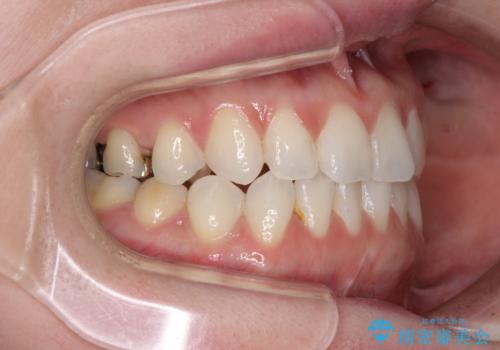

前歯のデコボコをすっきりと インビザライン矯正

- インビザライン

- 2年5ヶ月

- 前歯のデコボコを治したいとのことで来院された患者様です。

下顎が前方位にある方であったため、下顎の歯列全体の後方移動とIPR(歯と歯の間を削る)によってデコボコが解消するように設計し、インビザラインにより治療を行うこととしました。